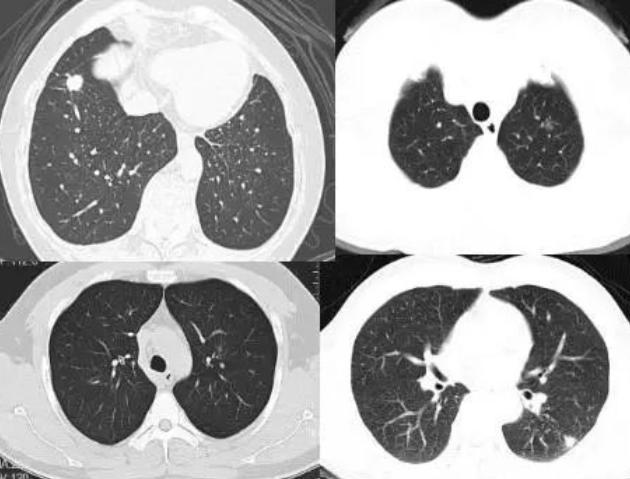

吸烟者的肺部与健康肺的区别

令人震惊的吸烟者肺部对比揭秘

烟民的肺是如何"黑化"的?看完赶紧掐掉手中的烟